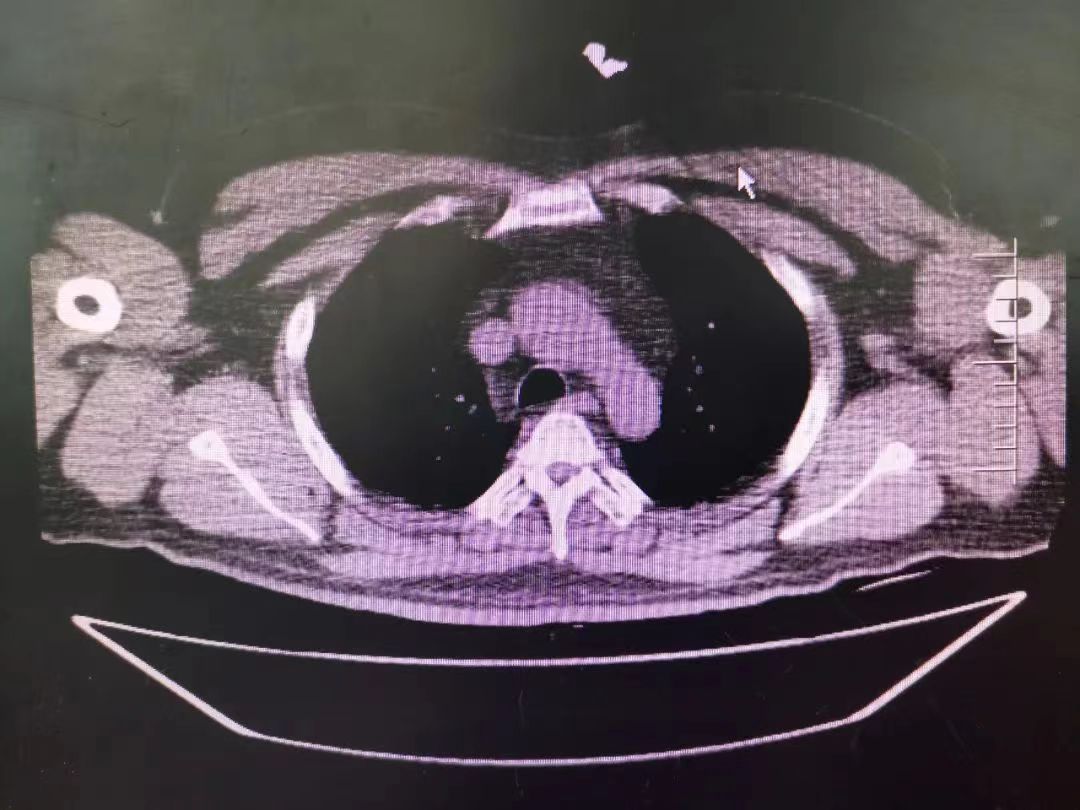

CT室門口,焦燥的家屬不停的走動著、等待著,看到醫(yī)生的到來,快速跑到醫(yī)生面前說:“醫(yī)生,快幫我看看,病人怎么樣”。陳醫(yī)生過去一看,一個體型偏胖的患者平躺在床上,一把剪刀齊根直插胸口觸目驚心,陳醫(yī)生不由眉頭一緊,轉(zhuǎn)身去看電腦CT影像 --剪刀斜著刺入胸骨,將胸骨完全穿透,刀尖距離心包約1-2mm,正下方是主動脈,大量心包積液?再一看,患者肥胖,脂肪組織多,不排除脂肪偽影??紤]患者血壓相對平穩(wěn),由于緊張導(dǎo)致心率快,立刻安撫患者,讓其保持安靜,盡量避免咳嗽,避免深呼吸和過多運(yùn)動。隨即撥通了武小剛主任的電話:“主任,這有一位患者,銳器刺傷不排除已經(jīng)損傷到心臟,病人目前血壓平穩(wěn)”“嚴(yán)密監(jiān)測患者病情變化,準(zhǔn)備急診手術(shù),我馬上到”武主任說。